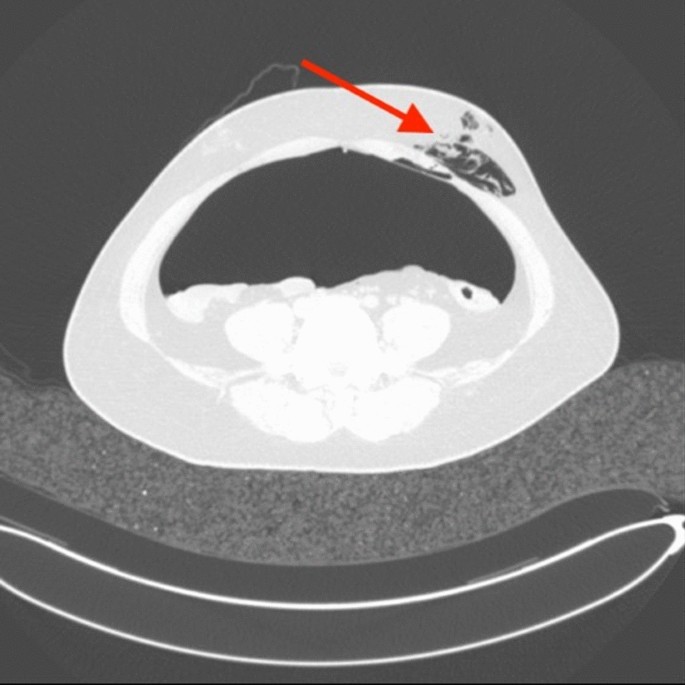

In the process of pneumoperitoneum, there are 22 patients developed complications of subcutaneous emphysema (Fig. 5), and the patient recovered well without sequelae in the follow-up treatment.

Image of the graded diagnosis of intestinal adhesions on CT with pneumoperitoneum. (A) Shows the CT image of the abdomen after pneumoperitoneum as level 0. (B) Shows the CT grade diagnosis of pneumoperitoneum as level 1. There is a single point adhesion between the local small bowel tube and the anterior abdominal wall. (C) Shows that the CT classification of pneumoperitoneum is level 2, showing that part of the intestinal tube and omentum tissue has multiple adhesions to the anterior abdominal wall. (D) Shows that the CT classification of pneumoperitoneum is level 3, and some diffuse adhesions of the anterior abdominal wall of the intestine and omentum tissue can be seen.